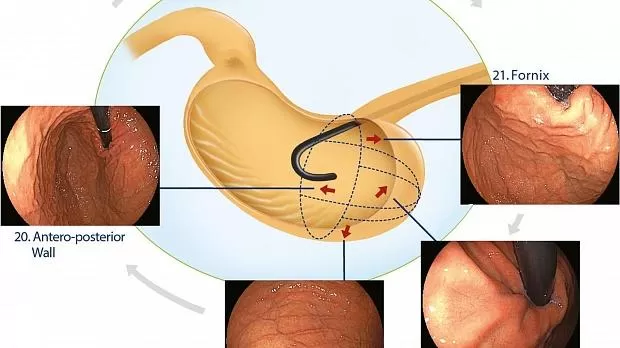

Верхняя треть

При вращении колесика вниз большая кривизна в его верхней части наблюдается в панорамной проекции, в области 19. Затем эндоскоп вводится с левой стороны, и в ретрофлексии переднезадняя стенка наблюдается на перевернутой оси, когда ретрофлексированный прицел можно увидеть с 12 до 2 часов, область 20. При перемещении прицела назад свод и часть кардии на передней и большей сторонах кривизны плотно фиксируются на перевернутой оси, область 21. В результате, При перемещении левой руки к правому плечу наблюдение кардии завершается тщательной фотодокументацией ее задней стороны и стороны малой кривизны, область 22 (рис. 7 ).